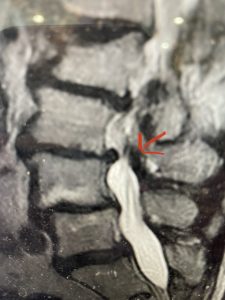

The next patient is a 71 year-old male with a two-year history of low back pain and lower extremity pain, numbness and weakness. His left leg was worse than the right. He had had five epidurals with no improvement. He also had tried physical therapy and medicines but nothing helped. He also felt that over the last three weeks he had gotten worse. He also had recently had some decreased sensation of bladder fullness and difficulty with bowel movements. MRI revealed a very tight L2-5 stenosis with an extruded L3-4 disc fragment (Fig 3).

(Figs 3a) Sagittal (a) and Axial (b) T2-weighted lumbar MRI demonstrating severe spinal stenosis L2-5 (arrow)and extruded disc at L3-4 on axial image (arrow)

He had concentric severe stenosis with severe compression of the lateral recess and foramen at L3-4 secondary to the superimposed disc herniation. The fact that he had gotten worse with subtle cauda equina features with an extremely tight canal, he underwent a decompressive laminectomy. We also augmented his laminectomy with an in situ fusion from L3-5 as he was relatively young, with more time to reform arthritis, and had been unstable enough to extrude a disc fragment. By placing “bone dust” or bone material along the sides of the spine, specifically laying it across the transverse processes after they have been drilled to bleeding bone, you provide an environment where bone formation is induced to connect the segments, stabilize them, and thereby reduce the signal to make more arthritis as that signal is still present despite the laminectomy. What was interesting was that we encountered a large extruded disk fragment that was significantly contributing to his compression which is often not found in patients in this age bracket. Post operatively he had much improvement of leg pain.